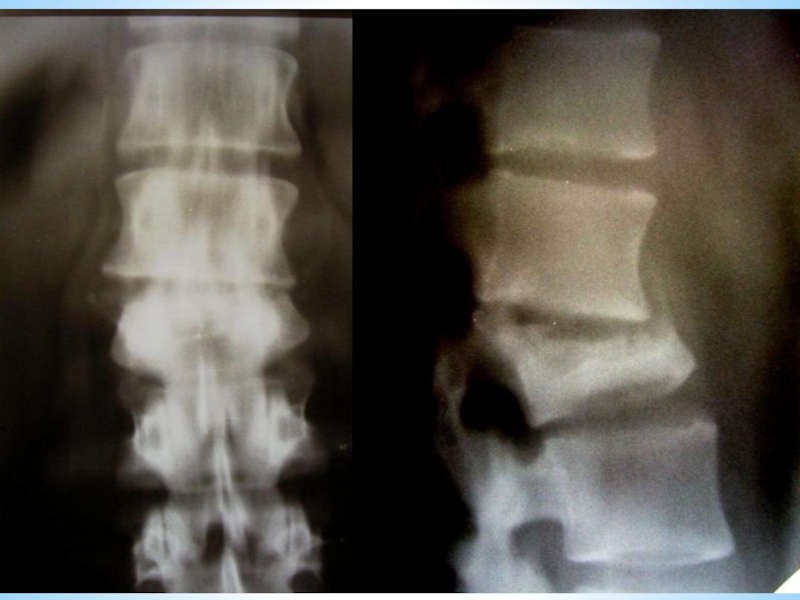

Рентгенодиагностика туберкулезного коксита

ранний признак — остеопороз костей, расширение теней межмышечных прослоек;

симптом асимметрии костей малого таза (симптом Пинхасика) в результате неправильного положения больного на спине (утолщение сустава на больной стороне, атрофия мышц или болевая контрактура).

Позднее — очаг поражения в одной из костей сустава. Отмечаются деформации суставных концов у детей — увеличение ядра окостенения головки бедра, уплощение вертлужной впадины (симптом Краснобаева). Сужение суставной щели; в некоторых случаях частичное нарушение контуров костей, затем их разрушение.

уплотнение тени сумки сустава, расширение межмышечных прослоек между сумкой, ягодичными мышцами, приводящими мышцами бедра (симптом Будинова — Ланге)

расширение тени запирательной мышцы (симптом Хефке —Тернера).

Появляется утолщение подкожной клетчатки на всей конечности (симптом Александрова)